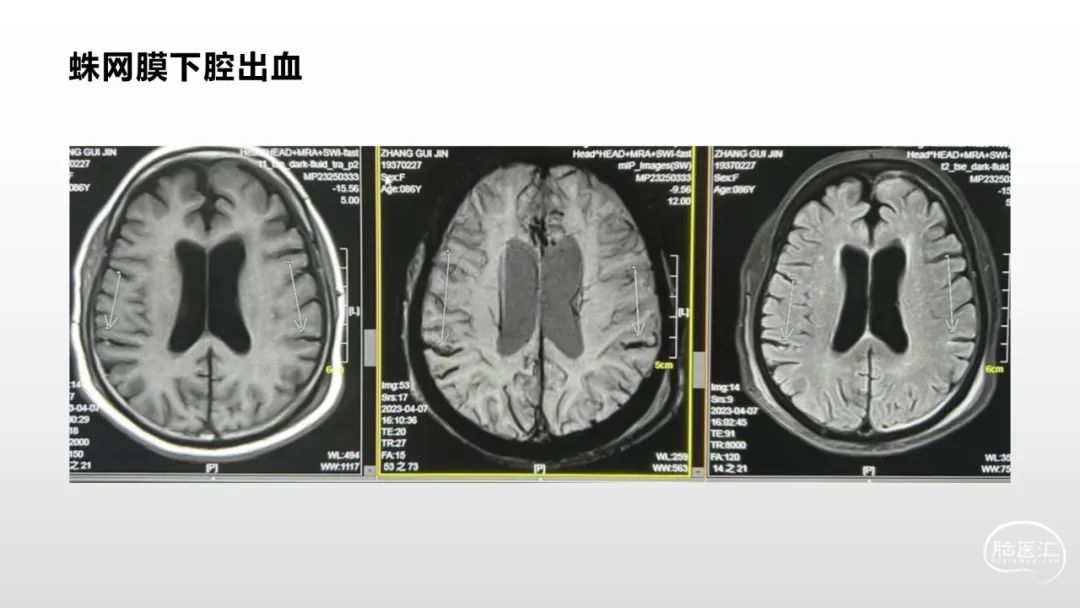

颅脑影像诊断基础知识讲座:脑膜病变